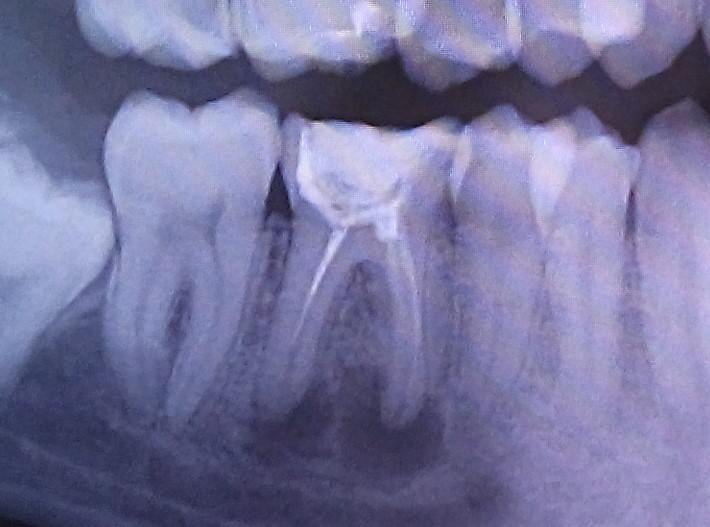

Киста зуба — это не просто полость у корня, а очаг хронического воспаления, который может долго оставаться бессимптомным, но при этом разрушать кость и ткани вокруг зуба. На ранней стадии, когда стенки образования еще размыты, лечение особенно эффективно. В этот период организм лучше отвечает на терапию, выше шанс полного восстановления тканей, и меньше риск осложнений. Но почему на снимке через неделю после начала лечения киста больше, чем в период обследования? Рост кисты после начала лечения не всегда указывает на неудачу терапии, а может быть естественным этапом в развитии воспалительно-регенеративного процесса.

Этап естественного созревания кисты. Если киста была вначале очень молодой, на что указывают размытые стенки на снимке, то по мере формирования она приобретает четкие контуры и может визуально увеличиваться. Это не означает ухудшения, а наоборот, может быть переходом из активной стадии в стабильную, инкапсулированную форму, с последующим самоугасанием или рассасыванием.

Киста корней зуба